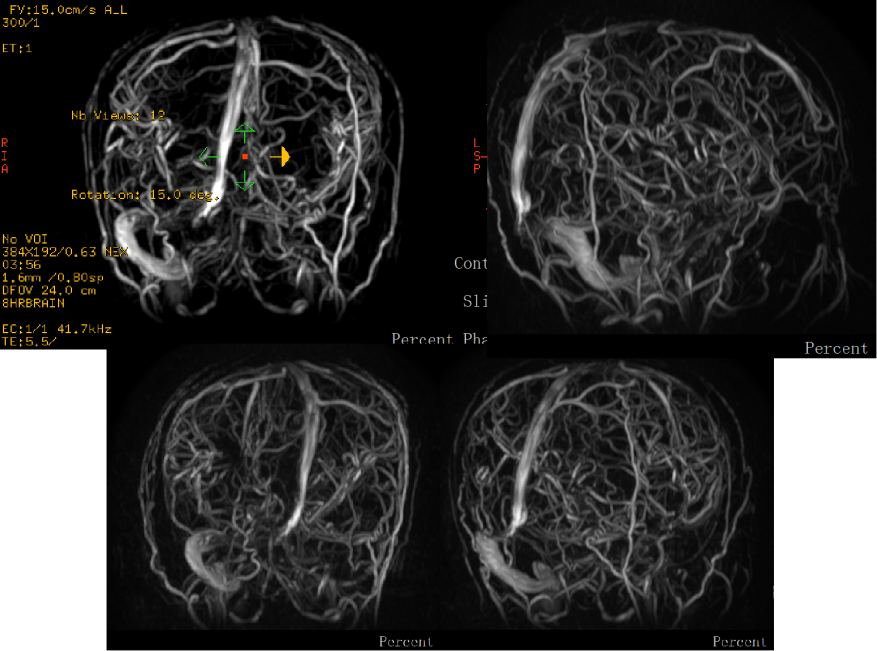

术前影像学资料

患者入院急诊完善MRV提示:左侧横窦、乙状窦、直窦血流信号充盈缺损,考虑静脉窦血栓形成(图二)。

术后1月患者随访MRV:MRV可见右侧横窦、乙状窦可见血流信号,较前好转。